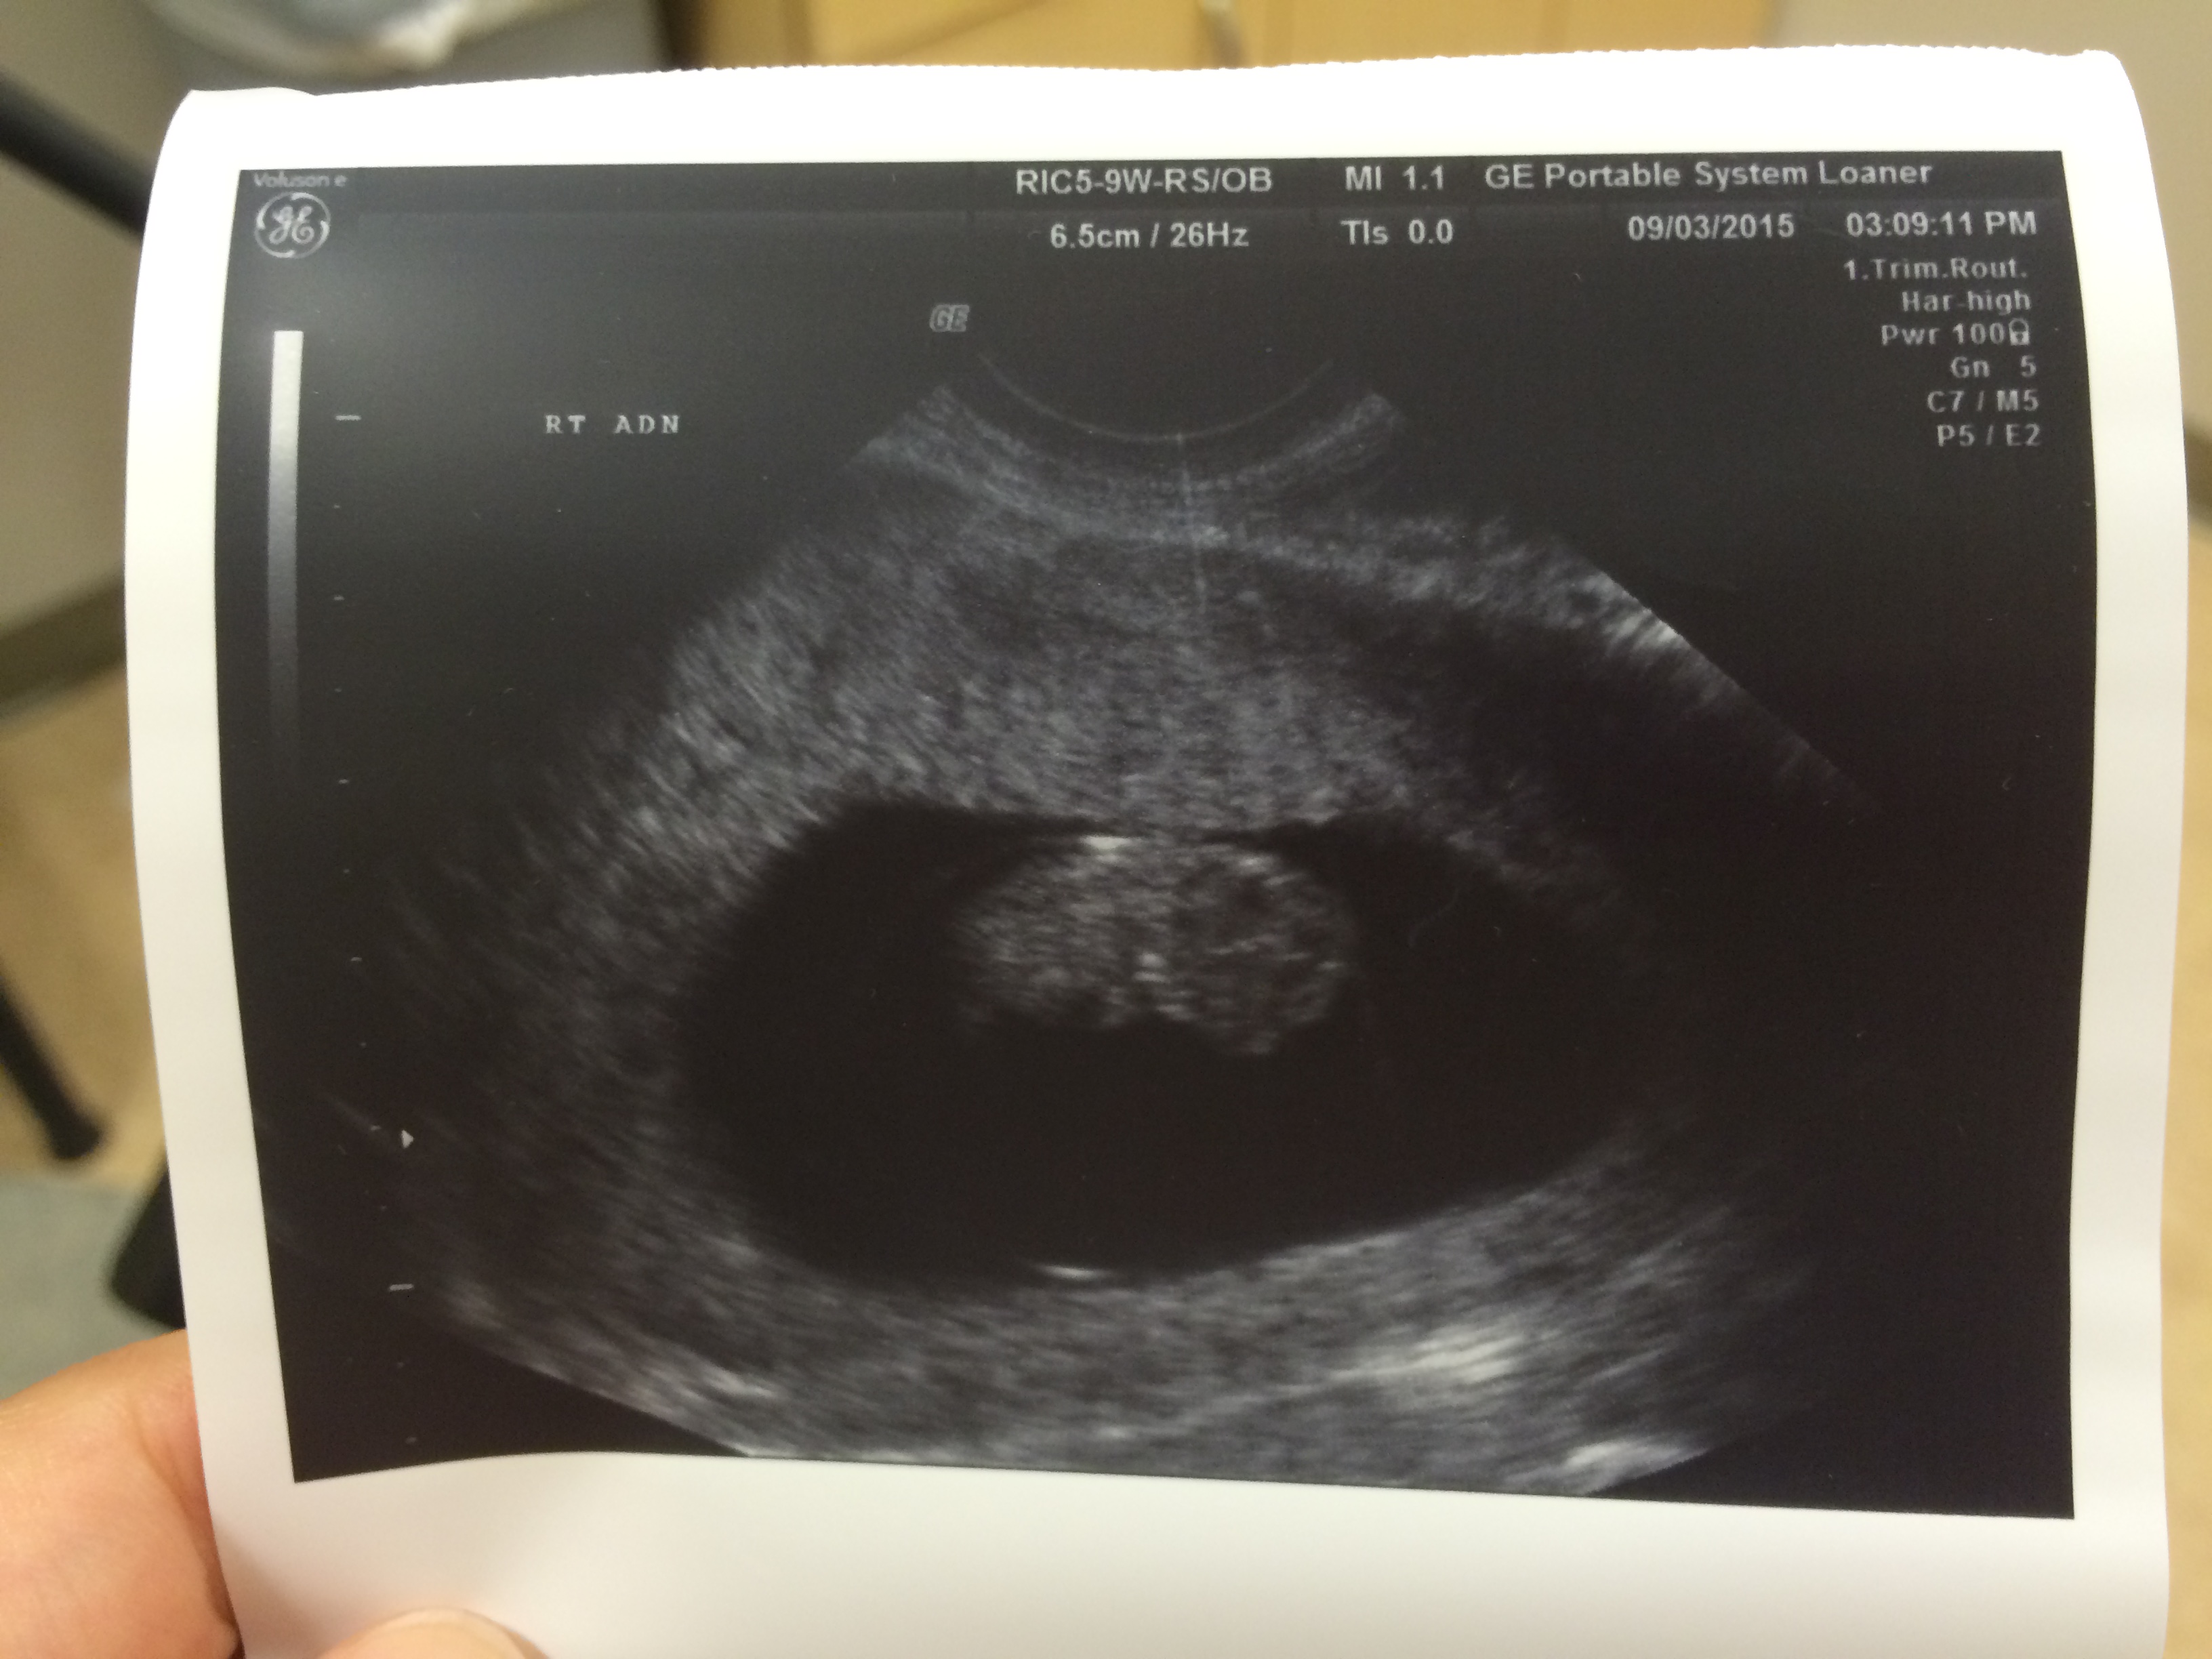

1st Pre-Natal Appointment

Today Dennis and I had our first doctor’s appointment to check on the baby. Despite all of my worry over the past month, there is indeed a little bean in my belly!